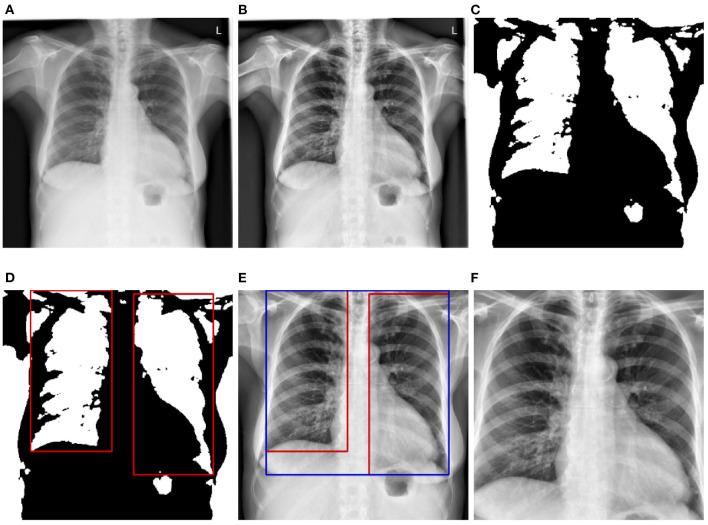

In recent years, several deep learning approaches have been successfully applied in the field of medical image analysis. More specifically, different deep neural network architectures have been proposed and assessed for the detection of various pathologies based on chest X-ray images. While the performed assessments have shown very promising results, most of them consist in training and evaluating the performance of the proposed approaches on a single data set. However, the generalization of such models is quite limited in a cross-domain setting, since a significant performance degradation can be observed when these models are evaluated on data sets stemming from different medical centers or recorded under different protocols. The performance degradation is mostly caused by the domain shift between the training set and the evaluation set. To alleviate this problem, different unsupervised domain adaptation approaches are proposed and evaluated in the current work, for the detection of cardiomegaly based on chest X-ray images, in a cross-domain setting. The proposed approaches generate domain invariant feature representations by adapting the parameters of a model optimized on a large set of labeled samples, to a set of unlabeled images stemming from a different data set. The performed evaluation points to the effectiveness of the proposed approaches, since the adapted models outperform optimized models which are directly applied to the evaluation sets without any form of domain adaptation.

近年来,几种深度学习方法已成功应用于医学图像分析领域。更具体地说,已经提出并评估了不同的深度神经网络架构,用于基于胸部X光图像检测各种病变。虽然所进行的评估显示出非常有前景的结果,但大多数评估都包括在单个数据集上训练和评估所提出方法的性能。然而,在跨域设置中,此类模型的泛化能力相当有限,因为当在源自不同医疗中心或根据不同协议记录的数据集上评估这些模型时,会观察到显著的性能下降。性能下降主要是由训练集和评估集之间的域转移引起的。为了缓解这个问题,在当前工作中提出并评估了不同的无监督域适应方法,用于在跨域设置中基于胸部X光图像检测心脏肥大。所提出的方法通过将在大量标记样本上优化的模型参数,适应于源自不同数据集的一组未标记图像,生成域不变特征表示。所进行的评估表明了所提出方法的有效性,因为经过适应的模型优于直接应用于评估集而没有任何形式域适应的优化模型。